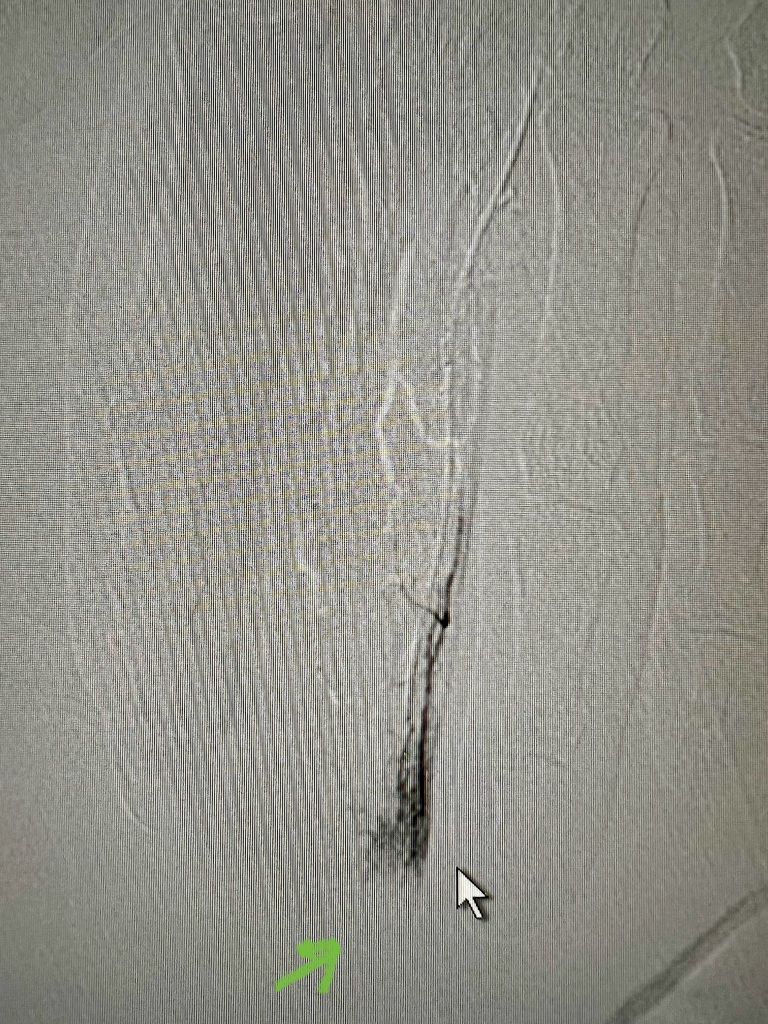

Lp(a) favors initiation of atherogenesis by modulating recruitment of inflammatory cells in the vessel wall. In vitro and animal studies have implicated lipoprotein(a) in key processes in atherosclerosis, including foam cell formation, smooth muscle cell proliferation, and plaque inflammation and instability.(4) Lp(a) blocks plasminogen conversion to plasmin, therefore plasmin mediated TGF-β activation is inhibited. TGF-β is an autocrine inhibitor of Smooth muscle cell growth.(12) Lp(a) increases atherosclerotic plaque vulnerability, vascular smooth muscle cell proliferation and adhesion of molecules, chemotactic factors and plasma cytokines. (Fig. 2) Moreover, Lp(a) enhances platelet activation and aggregation and inhibits fibrinolysis by inhibiting plasminogen activation.(13)

Fig. 2: The impact of lipoprotein(a) on atherosclerotic process and atherothrombosis. (source:Lampsas et al, 2023)